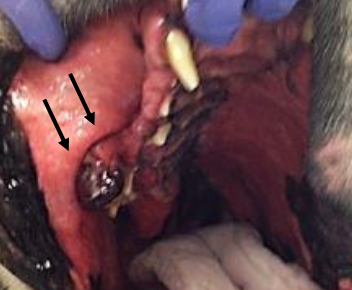

Describe the behavior of OMM

almost ALWAYS malignant

majority invades bone (locally invasive)

metastasis is COMMON

LNs and lungs most common

tonsils

other sites